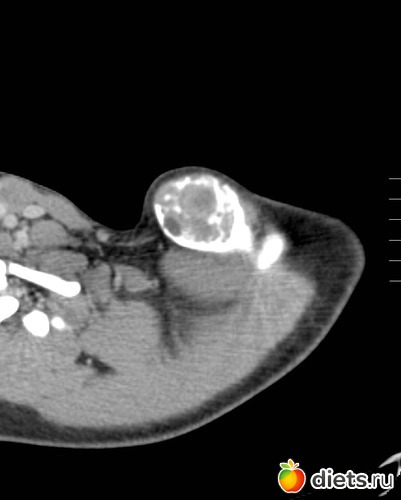

На МРТ врач обнаружил огромную кисту в области ключицы. Киста разрослась настолько, что косточка в ключице была вынуждена выгибаться как может.

Тянуть не буду с результами. Вообщем есть подозрение что это опухоль.

Злокачественная она или нет, пока не могут сказать. В любом случае её будут полностью удалять, вместе с частью сломанной косточки.